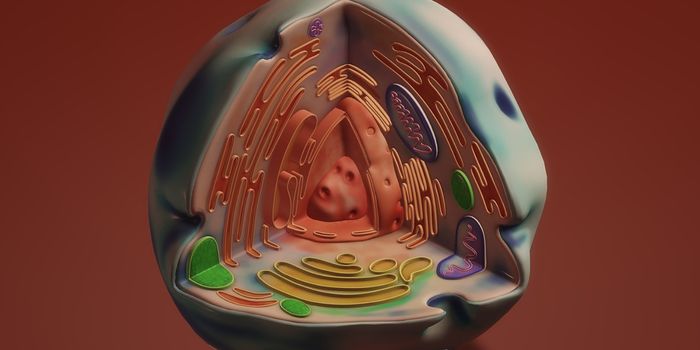

AUG 26, 2024Genetics & GenomicsCells are defined by the genes they express. In human cells, there are thousands of different protein coding genes, and ...

JUL 17, 2024Cell & Molecular BiologyAs the human body is developing, cells have to differentiate and specialize into certain specific types of cells, so the ...